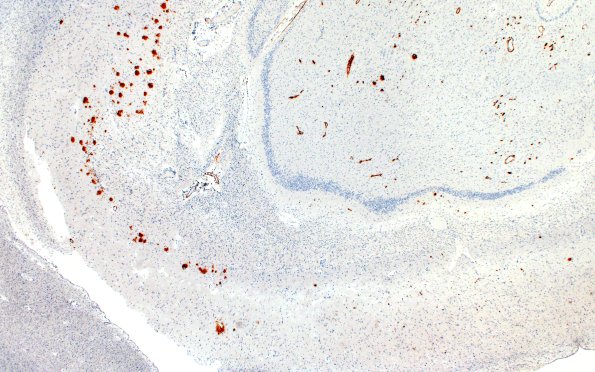

11E1,2 Amyloid immunoreactivity was variable even within the hippocampus. The amyloid deposition was prominent in the subarachnoid and parenchymal vasculature and within the cerebral cortex. (Beta amyloid, BAP IHC)